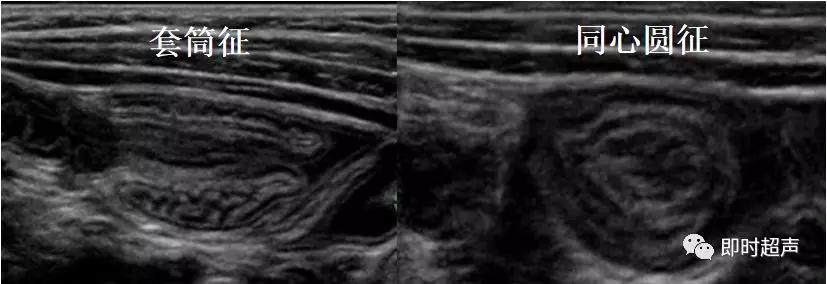

超声表现

低回声团:短轴 靶环征

长轴 套筒征

偏心 阑尾、息肉等

肠套叠超声表现

短轴切面同心圆征

长轴切面套筒征、短轴切面同心圆征